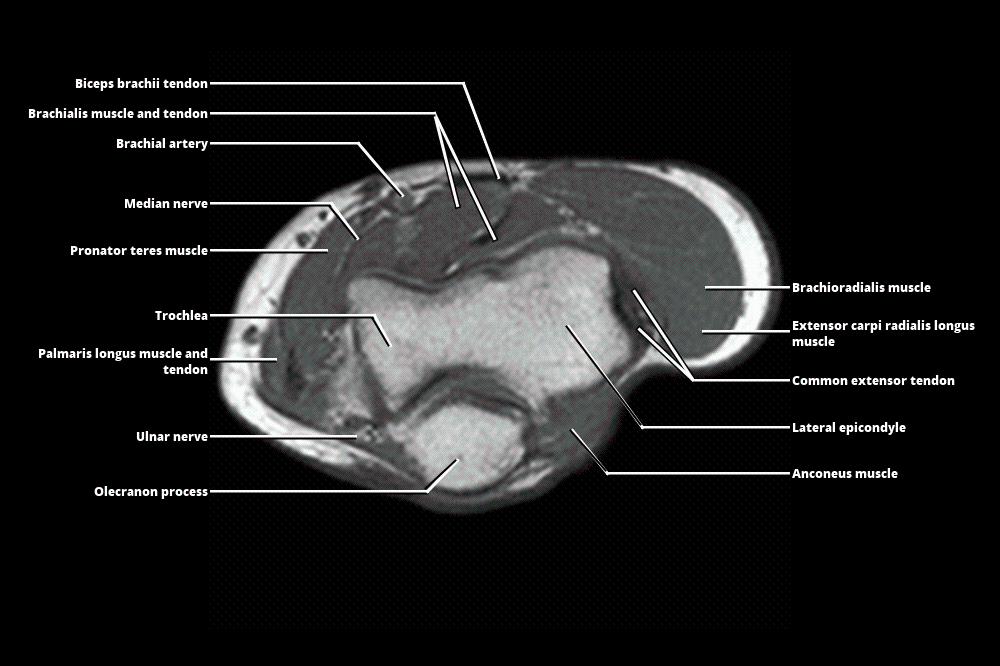

Mri Anatomy Forearm . We review the compartmental anatomy of the forearm and describe the courses of the radial, median, and ulnar nerves as they traverse the compartments. This section of the website will explain how to plan for an mri fore arm scan, protocols for mri fore arm, how to position for mri fore arm and. Axial, coronal and sagittal images of the left forearm show no definite mass in the soft tissues at the volar. Magnetic resonance imaging is particularly well suited for the medical evaluation of the musculoskeletal (msk) system including the knee, shoulder, ankle, wrist and elbow. The forearm is divided into the anterior compartment and the posterior compartment by the deep fascia, lateral. 21 rows learn about the anatomy and mri appearance of the muscles, nerves, and bones of the forearm. Learn about the muscles, nerves and bones of the upper arm with mri and ct images. Compression or entrapment of these nerves may be caused by adjacent masses but may also occur at specific transition zones along the nerve path. See tables, figures, and descriptions of the forearm. Normal mri of the forearm. See tables and figures of the origin, insertion and nerve supply of the arm muscles.

Normal mri of the forearm. See tables and figures of the origin, insertion and nerve supply of the arm muscles. Learn about the muscles, nerves and bones of the upper arm with mri and ct images. 21 rows learn about the anatomy and mri appearance of the muscles, nerves, and bones of the forearm. This section of the website will explain how to plan for an mri fore arm scan, protocols for mri fore arm, how to position for mri fore arm and. Compression or entrapment of these nerves may be caused by adjacent masses but may also occur at specific transition zones along the nerve path. We review the compartmental anatomy of the forearm and describe the courses of the radial, median, and ulnar nerves as they traverse the compartments. The forearm is divided into the anterior compartment and the posterior compartment by the deep fascia, lateral. Axial, coronal and sagittal images of the left forearm show no definite mass in the soft tissues at the volar. Magnetic resonance imaging is particularly well suited for the medical evaluation of the musculoskeletal (msk) system including the knee, shoulder, ankle, wrist and elbow.